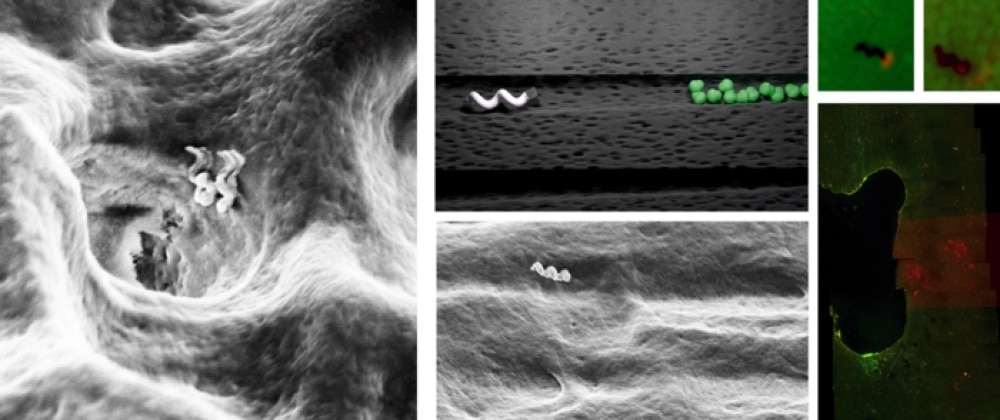

Авторы получили крошечные спиральные структуры из диоксида кремния, покрытые тончайшим слоем железа. Металлическая поверхность позволяет им реагировать на внешнее магнитное поле, а спиральная форма — двигаться под этой силой, буквально вкручиваясь в среду. Ученые подтвердили это, инъецировав таких «наноботов» в образцы больных зубов (удаленные у реальных пациентов) и проследив за их перемещениями под микроскопом.

Слева — «наноботы» входят в каналец зуба. По центру внизу — снимок одного из них внутри канальца, наверху — то же изображение схематически. Справа — микрофотография, сделанная во время уничтожения микробов теплом: живые клетки бактерий окрашены зеленым, мертвые — красным / ©Theranautilus

Миниатюрные спиральные устройства смогли проникнуть даже в самые глубокие и узкие ответвления зубных канальцев, на глубину вплоть до 2000 микрометров. При этом, варьируя частоту колебаний магнитного поля, можно заставить железо на поверхности «наноботов» разогреваться, убивая клетки бактерий, с которыми они вступают в контакт, и не нанося вреда тканям самого зуба. Кроме того, авторы испытали такой подход на мышах, подтвердив его работоспособность.